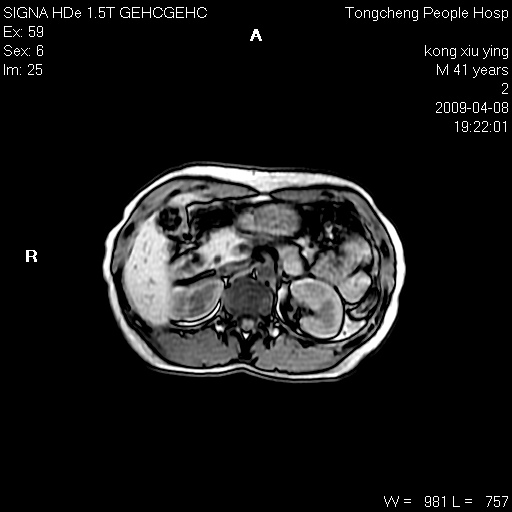

标题: CL1008:【经典】胆囊石榴籽样结石。

女,41岁。健康体检——彩超提示:胆囊显示不清。平素健康,无不适感。

腹部mr扫描及mrcp,图像如下: